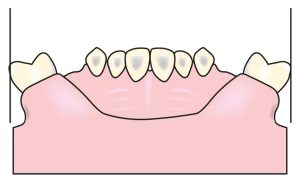

- The tuberosity region, which may become overly prominent either due to its natural anatomy or as a result of lateral expansion of the buccal bone following maxillary molar extractions (Figure 7-6),

These anatomical features should be carefully examined during cast surveying, as they may limit or complicate the intended path of insertion. In general, the bone in the premolar region is not as wide as in the molar region, and it is more tapered in the apical area compared to the crest. In such cases, attention must be paid to adapting the buccal flange of the prosthesis according to the undercut area.